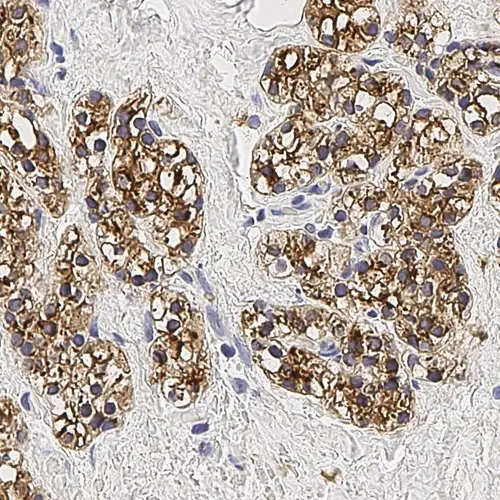

Human parathyroid adenoma: immunohistochemical staining for Parathyroid Hormone. Note membrane/cytoplasmic staining of tumor cells. Parathyroid Hormone: clone 105G7

The parathyroid glands are small, oval, endocrine glands closely associated with the thyroid gland. The parathyroid glands regulate serum calcium and phosphate levels via parathyroid hormone (parathormone). Parathyroid hormone raises serum calcium levels directly, by increasing the rate of osteoclastic reabsorption and promoting breakdown of the bone matrix, and indirectly, by increasing the renal tubular reabsorption of calcium ions and inhibiting the reabsorption of phosphate ions from the glomerular filtrate, and finally, by promoting the absorption of calcium from the small intestine. Parathyroid hormone is the most important regulator of blood calcium levels and is essential to life, whereas calcitonin appears only to provide a complementary mechanism for fine adjustment. Chief cells are the most abundant cells in the parathyroid gland and are responsible for the secretion of parathyroid hormone.